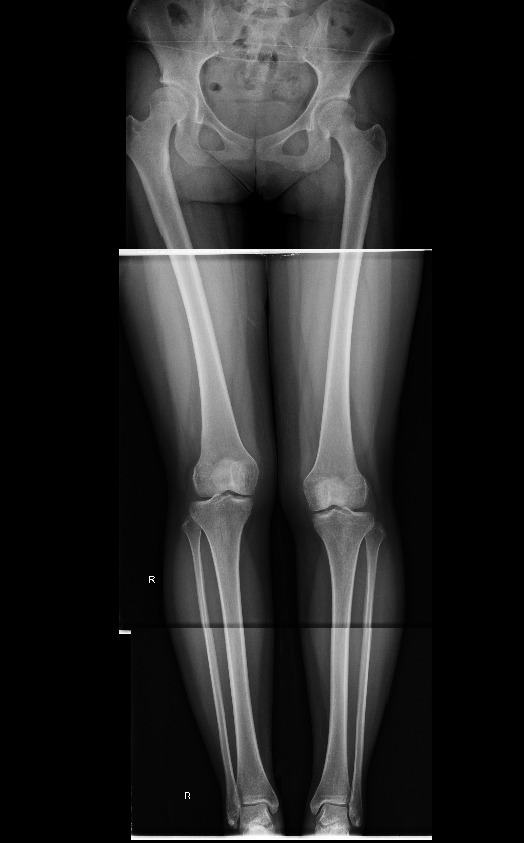

23살 여성

우측 경골이 2.5cm 더  길다. 그 결과로 골반, 척추의 측만증이 발생함.

1. 우측경골이 2.5cm더 긴상태로 자람.

2. 우측골반 상승